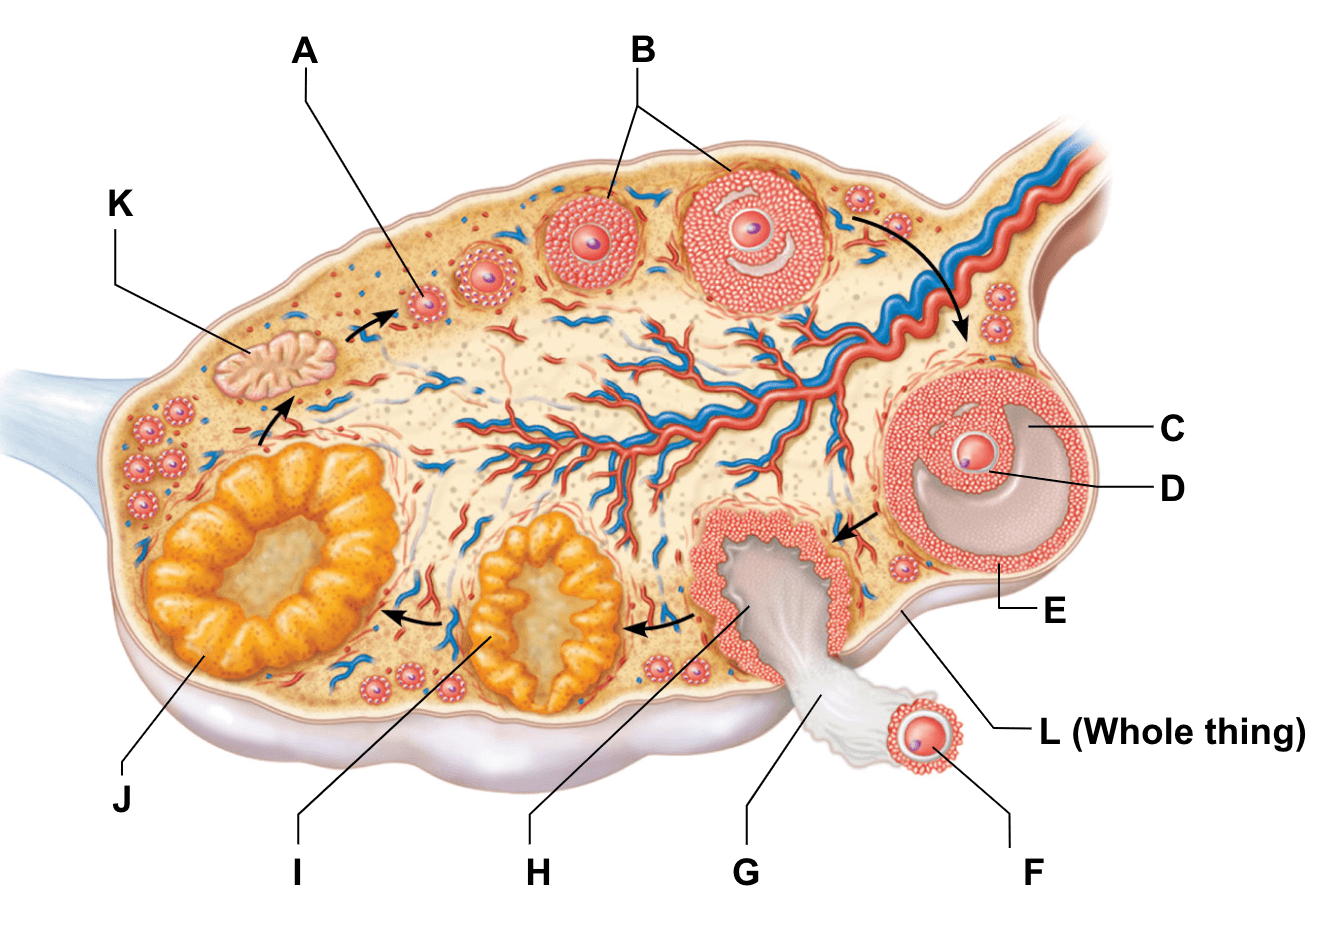

Созревание фолликула в яичнике: этапы и процессы

Раздел: Другие животные